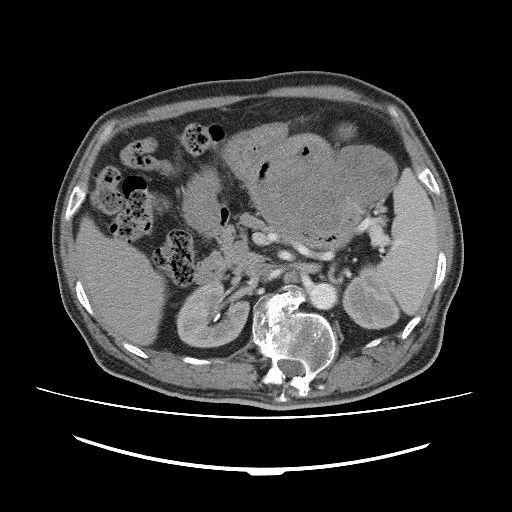

CT检查:CT扫描能够对GI无法完整显示的向腔外生长肿瘤的形态,大小清晰显示,尤其是多期增强扫描除了可以清晰的显示胃肠道管腔、管壁及肿块的形态外,还可以同时对管腔内的情况进行观察。扫描主要表现为胃肠道壁局限性增厚及软组织肿块,肿块呈圆形或分叶状,肿块大小多为4.5~8.5cm,随肿块增大,出现坏死、囊变或钙化率增高,导致密度不均匀,增强检查实性软组织成分多呈中度或明显强化,坏死囊变区无强化,肿瘤与周围组织器官界限模糊,可见存在侵袭性,如发生转移则支持恶性GIST。

CT检查特点:增强扫描肿瘤实质部分动脉期即有明显强化,静脉期持续强化,囊性部分无强化,静脉期强化可比动脉期更显著,坏死、囊变区无强化。